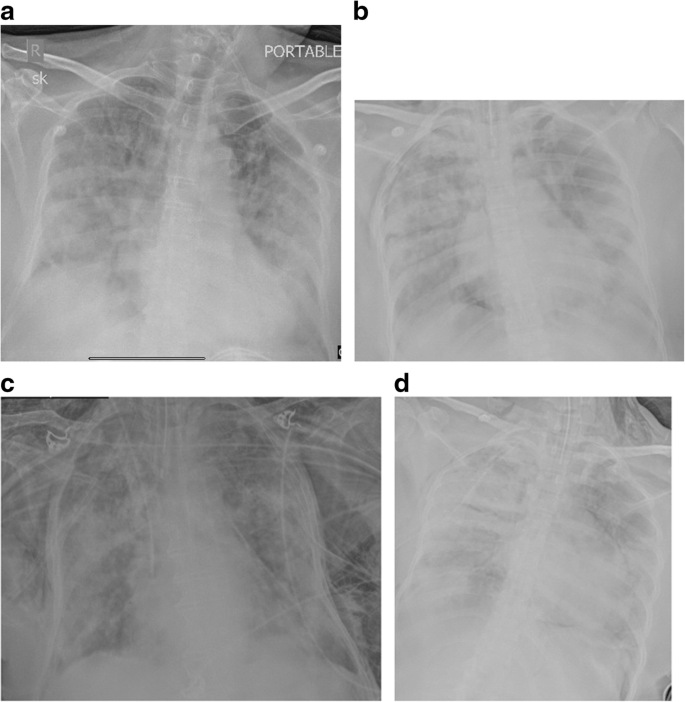

Fig. 1

figure 1

Chest X-ray AP portable in 4 different patients showing different lung findings in COVID-19 infection. Technical factors: 70 Kv and 20 mAs. Image a shows normal lungs. Image b shows peripheral consolidation on the right and peripheral lung opacities on the left. Image c shows peripheral ground glass opacification in mid and lower zones. Image d shows typical “batwing” appearance of peripheral consolidation

Sixty percent of the total X-rays were abnormal and showed unilateral or bilateral lung manifestations which included ground glass opacification, peripheral lung opacities, confluent consolidation, and reticular or small irregular opacities (Table 1). Additional features such as pneumothorax, pneumomediastinum, pleural effusion, and adenopathy were seen uncommonly. GGO (Fig. 1), either unilateral or bilateral, appeared most frequently in the abnormal X-rays (75% of abnormal x rays). In 81% of the 269 X-rays which showed GGO, GGO was an exclusive finding. PLO (Fig. 1) was next in frequency of appearance and seen in 88 X-rays (25%). Confluent consolidation (Figs. 1 and 2) was seen in 15% of the chest X-rays with findings. Pneumothorax and pneumomediastinum (Fig. 2) were present in only 3 out of the abnormal 358 X-rays (< 1%), as were pleural effusions. Adenopathy was not present in any chest X-ray.